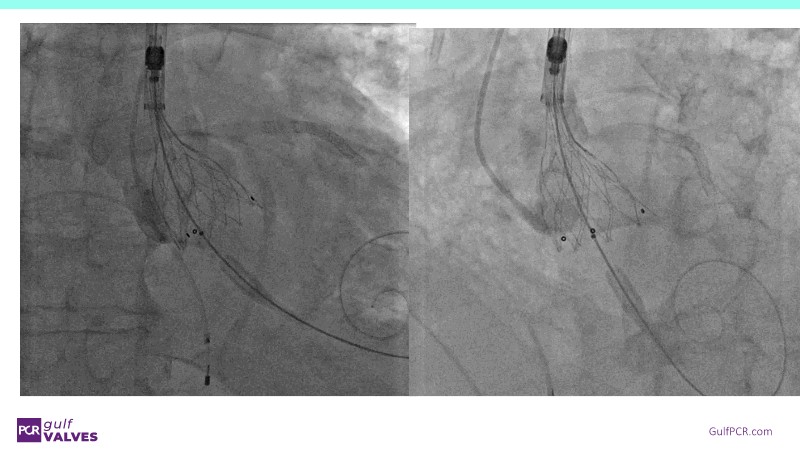

Discover a selection of cases showcasing the key features of the Navitor Valve System and its clinical applications. This session explores auxiliary access, the use of Navitor in alternative access and complex PCI, its performance in challenging peripheral anatomies, and innovative outcomes with the Vantage 30D system.